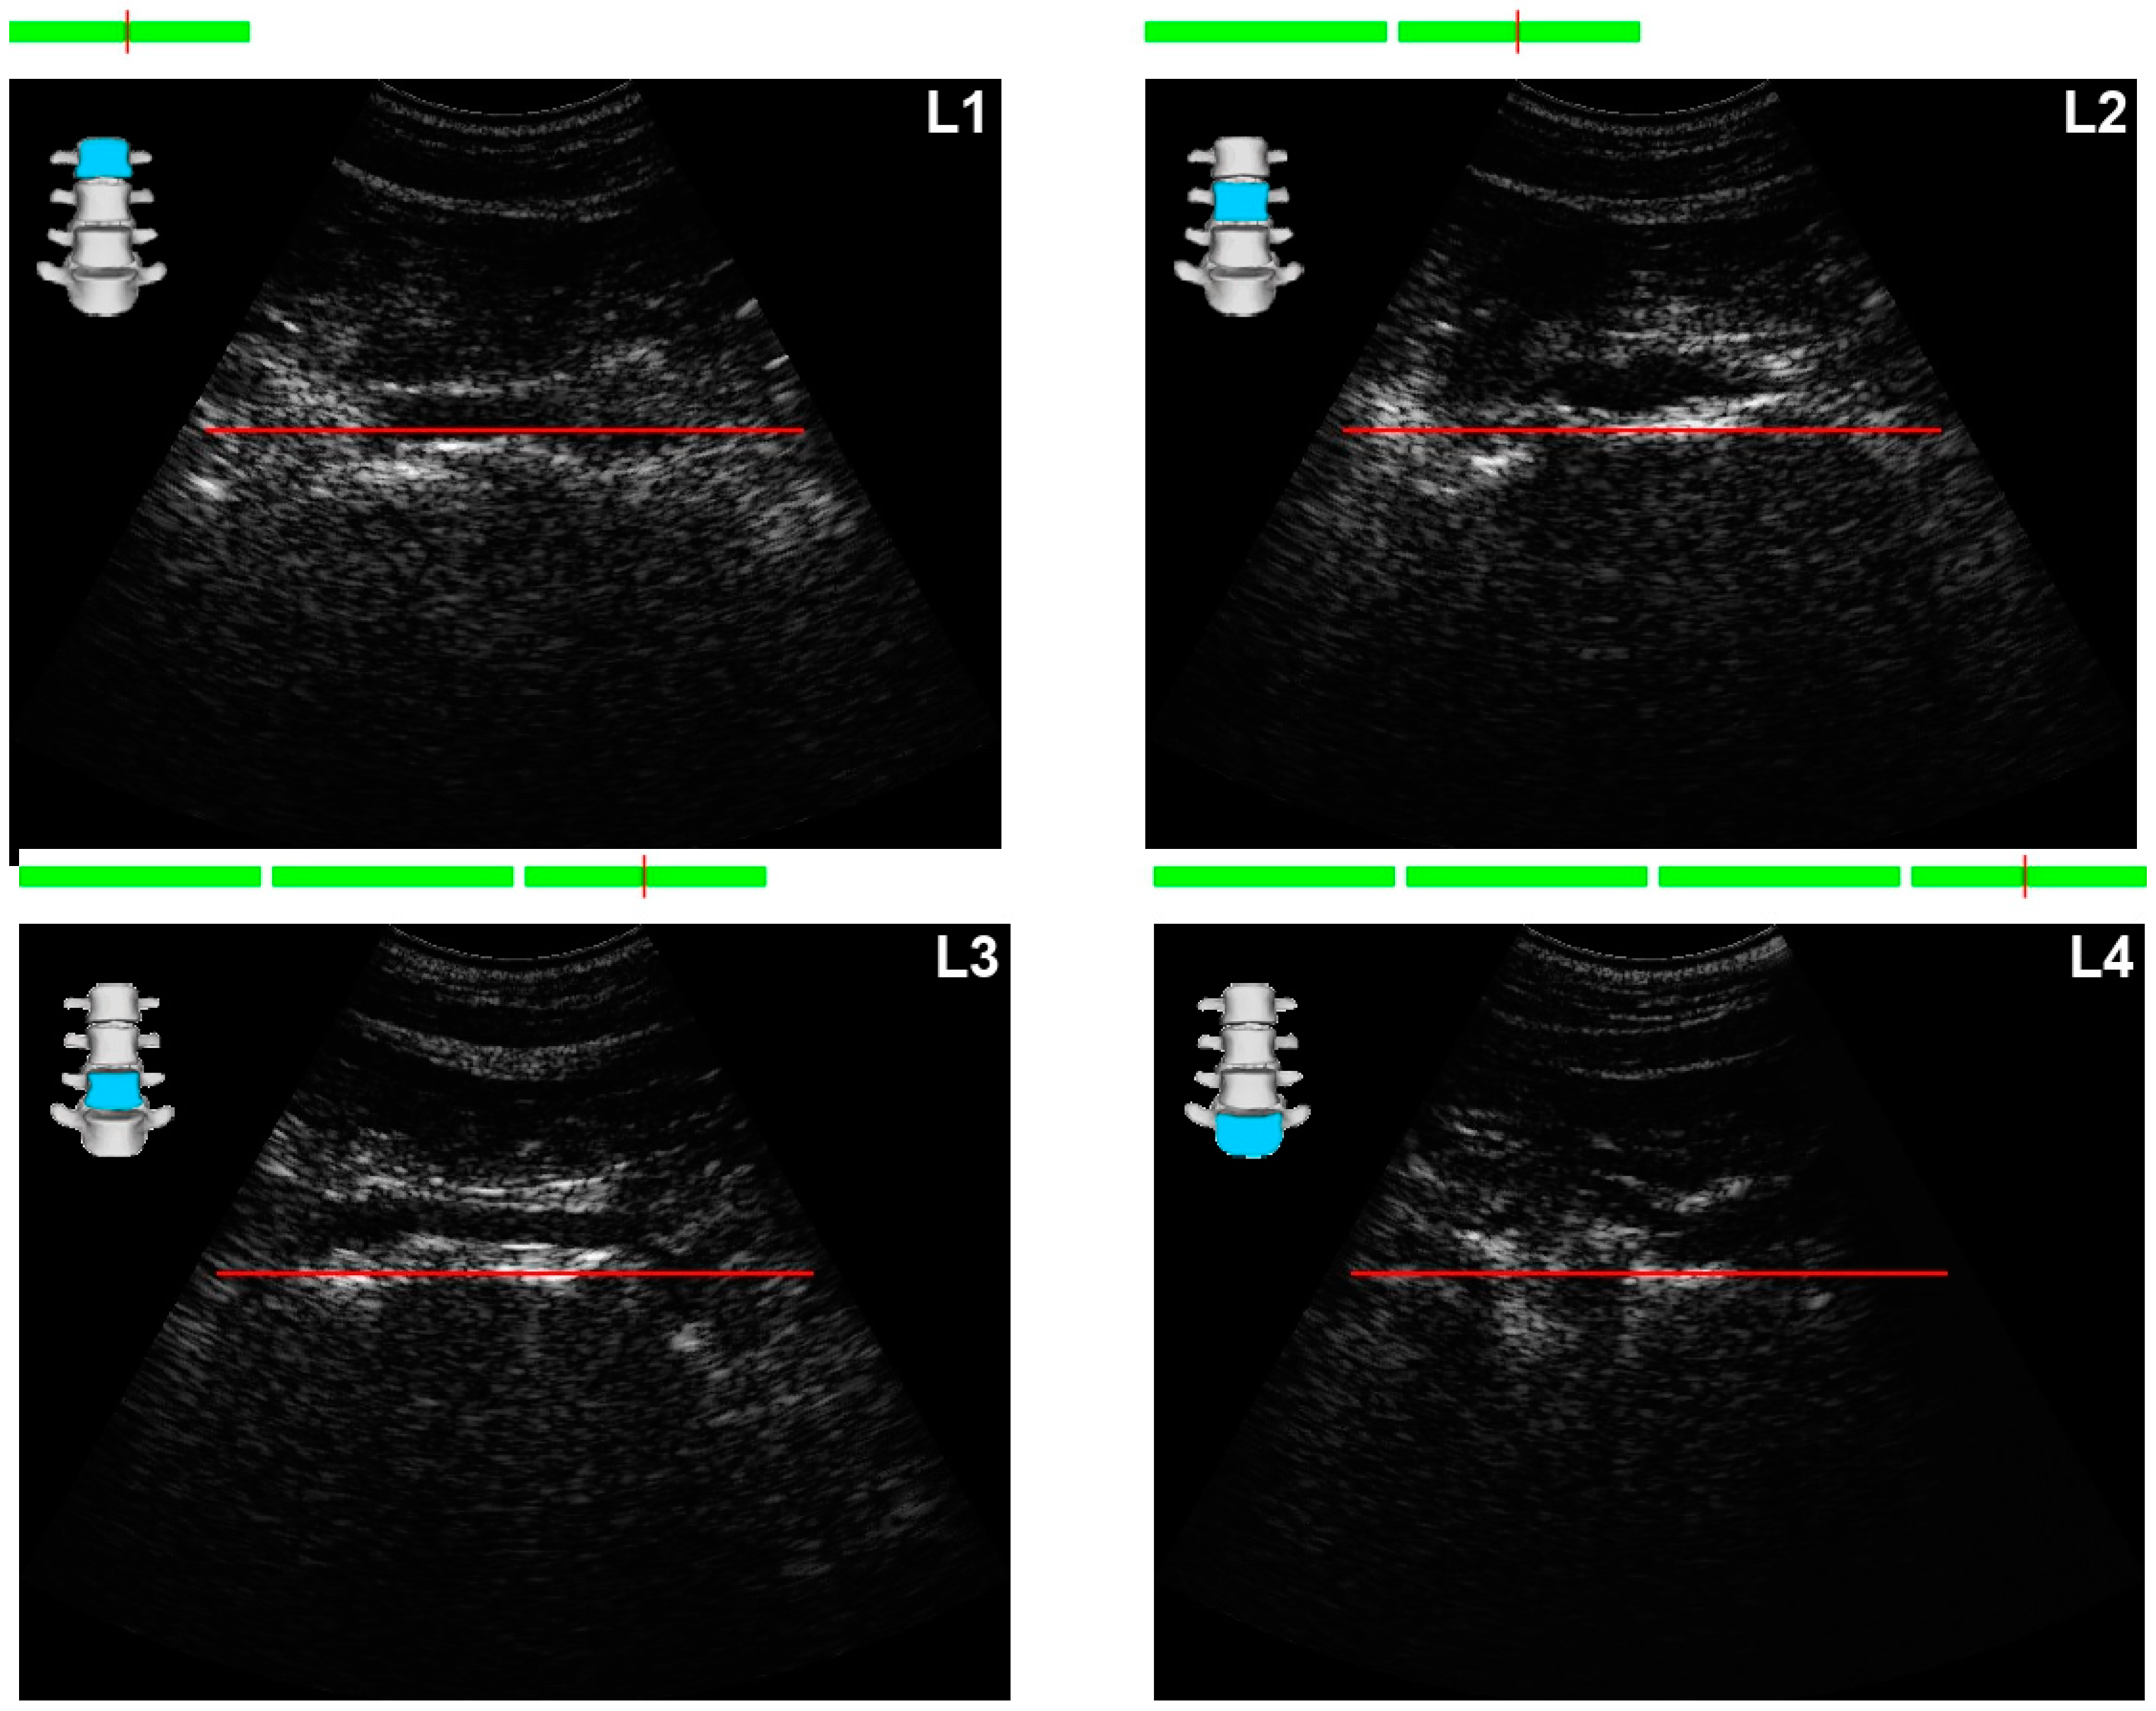

Positioning the Probe